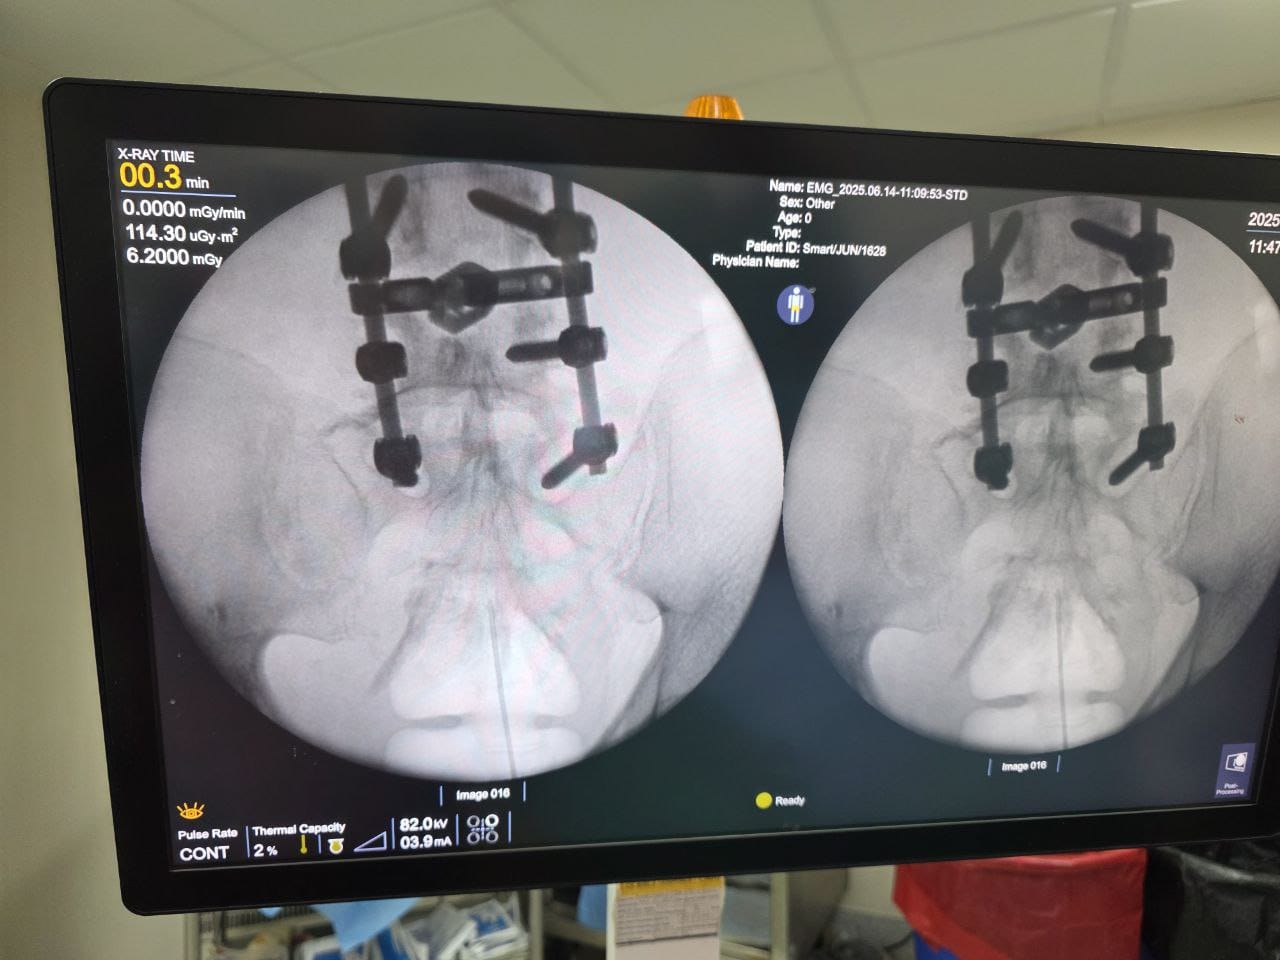

Procedures

Struggling with chronic pain? Get advanced, personalised pain management from Dr. Manish De, one of Kolkata’s leading pain specialists. From knee pain, heel pain, low back pain, frozen shoulder, migraines, cancer pain to post-TKR persistent pain—Dr. De offers safe, evidence-based treatments across multiple locations: